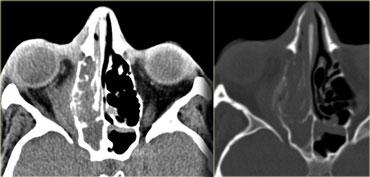

Vỡ nhãn cầu

Hình bên trái là hình ảnh của một bệnh nhân nhập cấp cứu với tình trạng sưng nề hốc mắt sau chấn thương.

Bệnh nhân này bị vỡ nhãn cầu, cụ thể là vỡ tiền phòng.

Là các bác sĩ chẩn đoán hình ảnh, chúng ta thường chú ý đến dịch kính khi nghi ngờ vỡ nhãn cầu, nhưng như vậy là chưa đủ.

Lưu ý rằng độ sâu của tiền phòng bị giảm.

Có tình trạng tăng tỷ trọng ở phía trước do xuất huyết tiền phòng (hyphema – máu trong tiền phòng).

Cũng cần lưu ý rằng thủy tinh thể bên phải bị mờ và giảm tỷ trọng nhẹ.

Đây được gọi là đục thủy tinh thể do chấn thương.

Có thể bạn sẽ kỳ vọng thủy tinh thể tăng tỷ trọng hơn, nhưng thực tế thường không phải như vậy.

Hình bên trái là hình ảnh CT của một bệnh nhân bị chấn thương mắt trái.

Hãy phân tích hình ảnh để tìm 5 dấu hiệu trước khi tiếp tục đọc.

Các dấu hiệu bao gồm:

- Tiền phòng nông hơn so với bên phải, gợi ý vỡ nhãn cầu.

- Tỷ trọng trong tiền phòng tăng, gợi ý xuất huyết tiền phòng (hyphema).

- Tỷ trọng của thủy tinh thể giảm, cho thấy bệnh nhân bị đục thủy tinh thể do chấn thương.

- Có vùng tăng tỷ trọng trong buồng dịch kính, gợi ý xuất huyết dịch kính.

- Nhãn cầu dẹt ở mặt sau, cho thấy có vỡ dịch kính kèm theo.

Vỡ nhãn cầu thường gặp nhất ở vị trí tiền phòng.